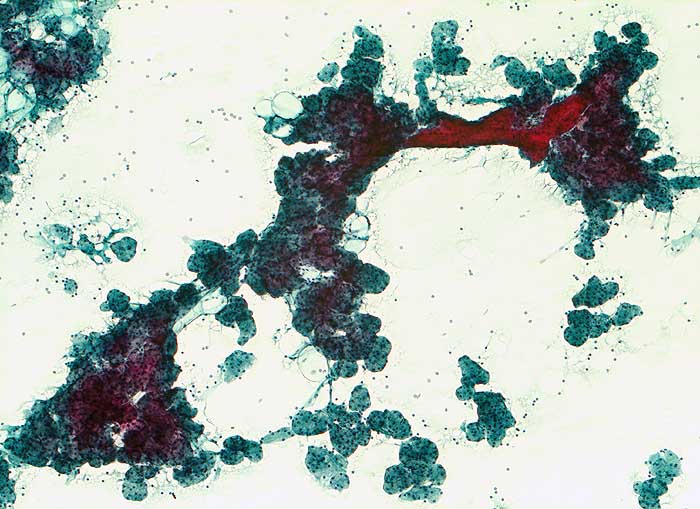

Bei der Sialadenose handelt es sich um eine nicht-entzündliche, nicht-neoplastische diffuse Schwellung der Parotis. Meist sind beide Seiten betroffen. Die Sialadenose kommt vor bei Malnutrition, Alkoholismus, endokrinen Erkrankungen, Diabetes mellitus, neurogenen Erkrankungen oder bestimmten Medikamenten (Antihypertensiva, Sympathomimetika). Die Punktion kann schmerzhaft sein. Die Speicheldrüsenazini messen durchschnittlich 60 bis 75 Mikrometer (Normal: 50 Mikrometer). Typisch sind einzelne sehr grosse Azini von bis zu 100 Mikrometer Durchmesser. Das Zytoplasma der Azinuszellen ist geschwollen und kann degranuliert sein. Eine Neoplasie oder Entzündungszellen sind nicht nachweisbar.